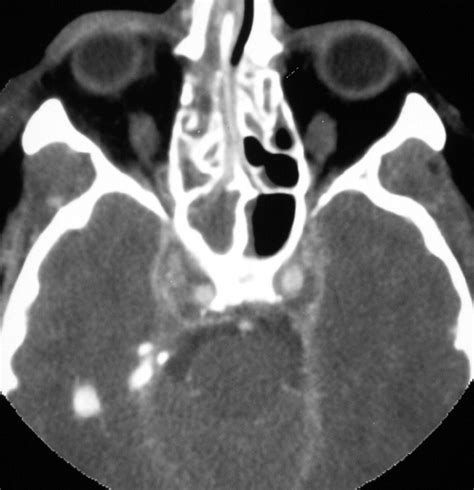

Diagnosing Cavernous Sinus Syndrome requires a high index of clinical suspicion and advanced imaging techniques. Physicians often utilize a combination of clinical evaluation and diagnostic testing to pinpoint the underlying etiology. Because the syndrome can be caused by various factors—from infections like sinusitis to malignant tumors or cavernous sinus thrombosis—the approach must be comprehensive.

CT Scan (Computed Tomography) Excellent for viewing bone involvement, particularly if the cause is related to paranasal sinus infection.

• Infections: Sinusitis, orbital cellulitis, or infections of the central face can spread through venous pathways into the sinus.